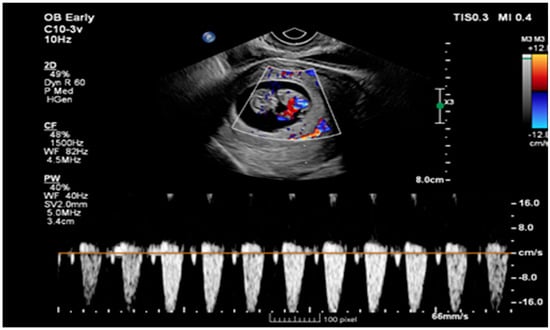

Ruptured Heterotopic Pregnancy: Laparoscopic Management, Preserving Intrauterine Viability

Pregnancy (HP), defined as the coexistence of intrauterine and ectopic gestations, is a rare condition, especially in spontaneous conception, but it is a life-threatening obstetric emergency when rupture occurs, with a reported maternal mortality rate of 0.03%. Diagnosis is often delayed because confirmation of an intrauterine pregnancy can mask clinical signs of a concurrent ectopic gestation. Early recognition and prompt surgical intervention are therefore critical to maternal safety and preservation of intrauterine viability. This case highlights the diagnostic challenges and successful management of a spontaneous ruptured heterotopic pregnancy. Case presentation: A 34-year-old Middle Eastern woman, gravida 4, with a spontaneous conception, presented with sudden severe lower abdominal pain and signs of acute hemoperitoneum (hypotension, tachycardia, and marked peritoneal signs). Transvaginal ultrasound demonstrated a viable intrauterine pregnancy at 9 weeks 4 days gestation, together with a ruptured left tubal ectopic pregnancy of similar gestational age. The patient underwent urgent laparoscopic left salpingectomy with evacuation of approximately 1200 mL of intraperitoneal blood and clots. Postoperatively, she developed significant anemia (hemoglobin drop from 11.2 g/dL on admission to 6.5 g/dL) requiring transfusion of four units of packed red blood cells. Serial ultrasonographic follow-up confirmed ongoing viability of the intrauterine pregnancy, which ultimately resulted in a live birth at term. Progressive resolution of the postoperative pelvic hematoma was also noted. Conclusions: Ruptured heterotopic pregnancy remains a diagnostic and therapeutic challenge. This case, along with a synthesis of the contemporary literature, demonstrates that a high clinical index of suspicion, timely ultrasound diagnosis, and immediate minimally invasive surgical management are paramount. Furthermore, rigorous postoperative monitoring and resuscitation, including targeted transfusion, are essential to achieve maternal stabilization while allowing continuation of a viable intrauterine pregnancy, with reported live birth rates exceeding 70% following timely intervention. Full article